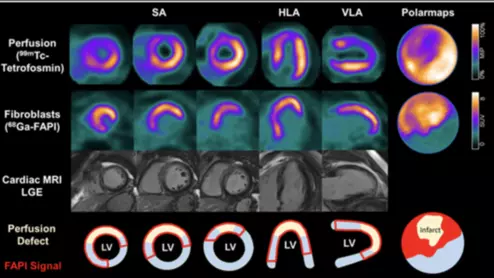

American Society of Echocardiography (ASE) President David H. Wiener, MD, FACC, FAHA, FASE, director of clinical operations at the Jefferson Heart Institute, and a clinical professor of medicine at Thomas Jefferson University, explains the growing number of multimodality cardiac imaging experts and how imaging societies need to change to meet their needs.

ASE President David Wiener detailed some of the many ways imaging societies need to adapt now that so many imagers are specializing in multiple modalities. It may be time to change how annual conferences are scheduled, for example, so that the costs of travel are easier to manage.